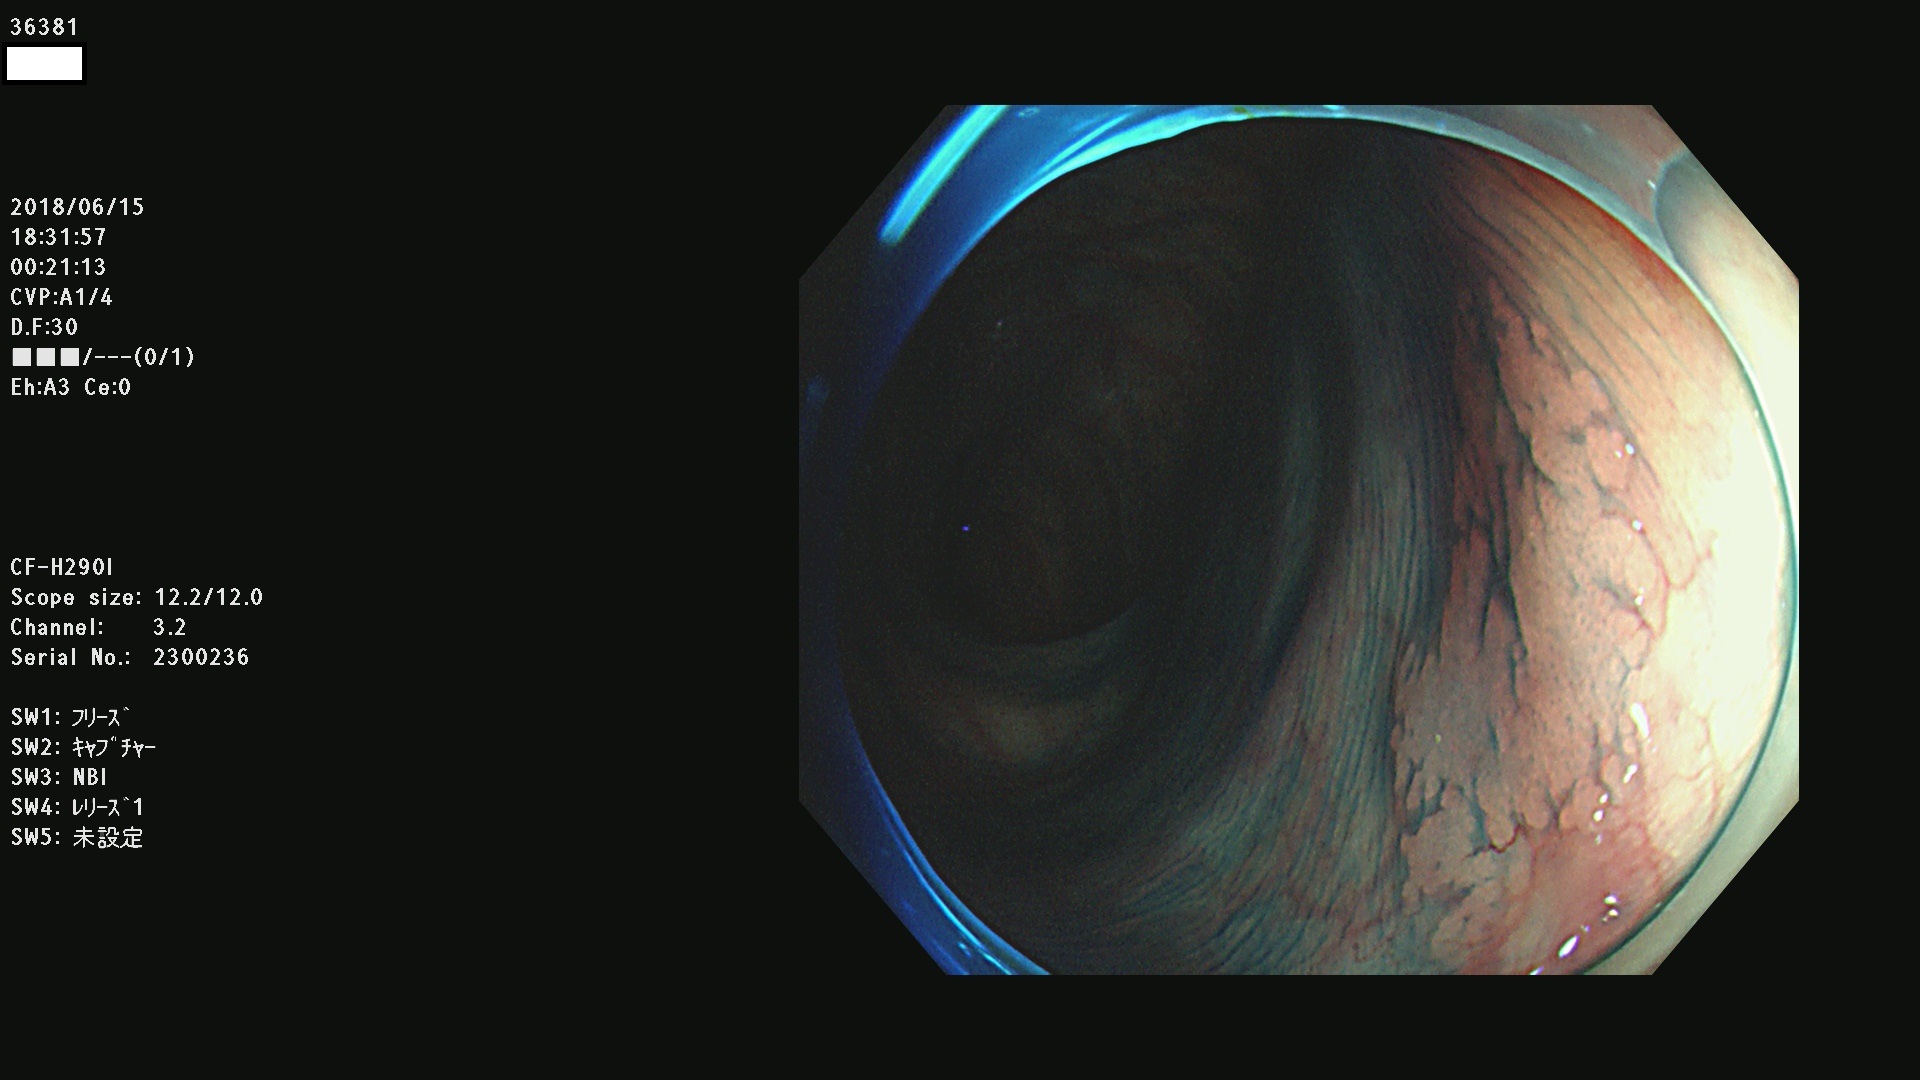

腺腫発見率 68 % (カルテ番号 36300〜36399の100名の方の検査結果で集計)大腸癌検診最新情報

以下のカルテ番号の方に腺腫(Adenoma,Group3〜5)が見つかりました(集計法)

36300 36302 36305 36306 36307 36308 36310 36311 36312 36313 36314 36315 36316 36318 36321 36322 36324 36325 36326 36327 36330 36332 36333 36334 36335(SSAPのみ) 36337 36338 36339(SSAPのみ) 36340 36341 36342(SSAPのみ) 36343 36344 36346 36348 36349 36351 36353 36354 36355(SSAPのみ) 36356 36357 36358 36359 36364 36365 36366 36367 36370 36374 36376 36379 36381 36382 36383 36384 36385 36387 36388 36389 36390 36392 36393 36395 36396 36398 36399

発見困難で危険性の高い平坦型病変(上記100名より抽出) ![]()